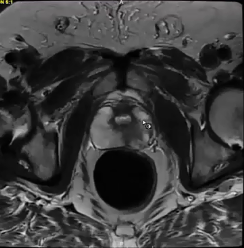

urethral tumor, urothelial carcinoma, PET, CT, palliative treatment, mediastinal nodes, biopsy, prostate gland, PSMA, false positive, pelvis with nodes, bone lesions, PSA, bladder